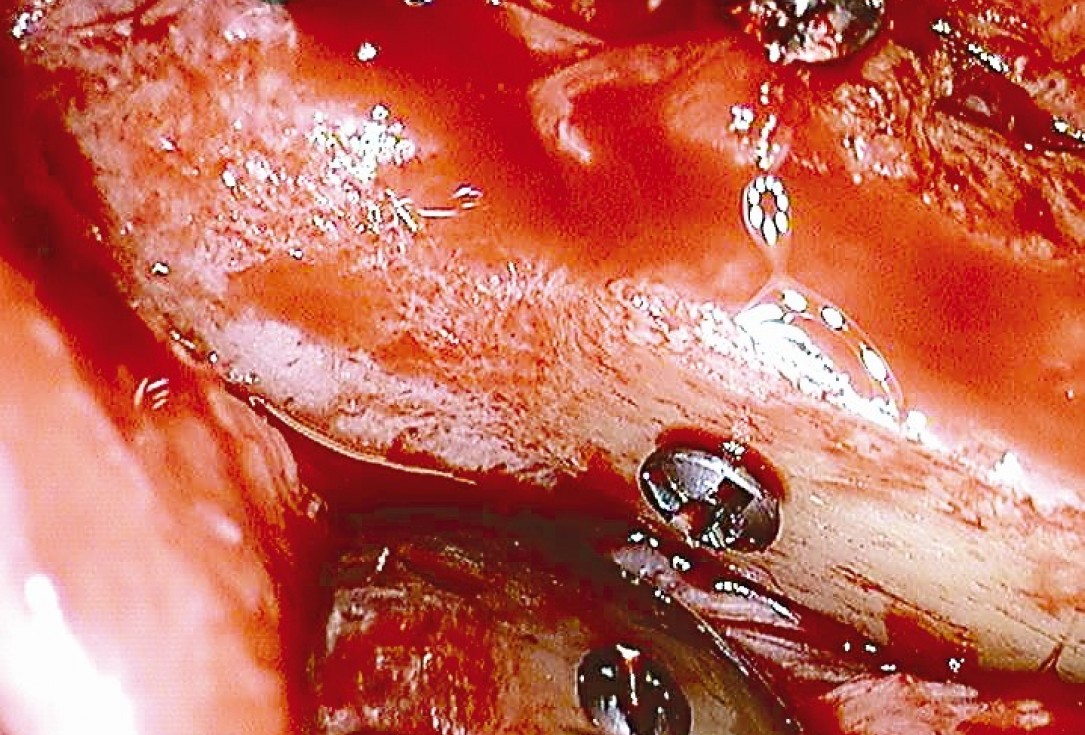

Preparation of a single tooth defect with severely resorbed vestibular wall